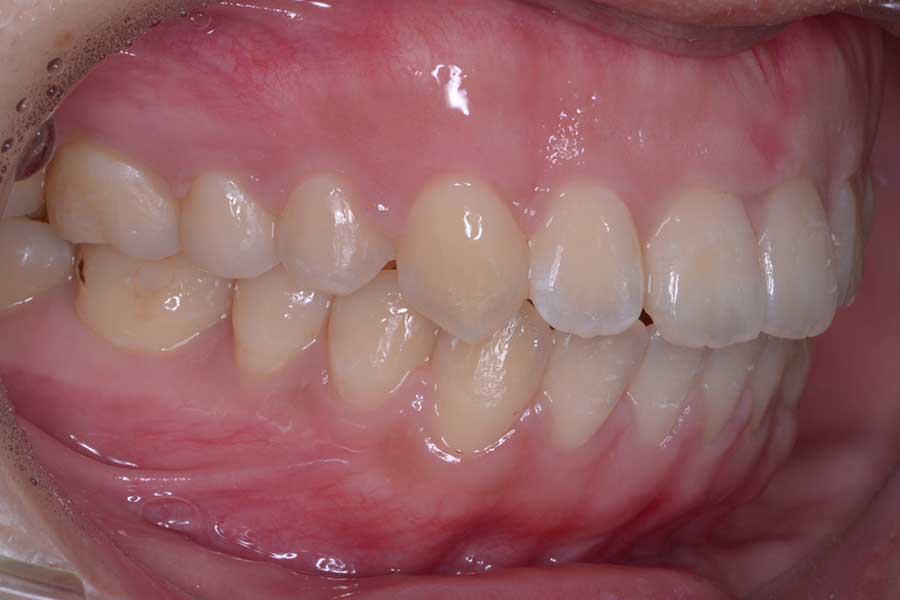

【20代女性】捻じれと段差と咬み合わせを治したい

• 治療後

主訴 捻じれと段差と咬み合わせを治したい

期間 10か月

治療内容 上下顎ラビアル矯正(表側矯正)